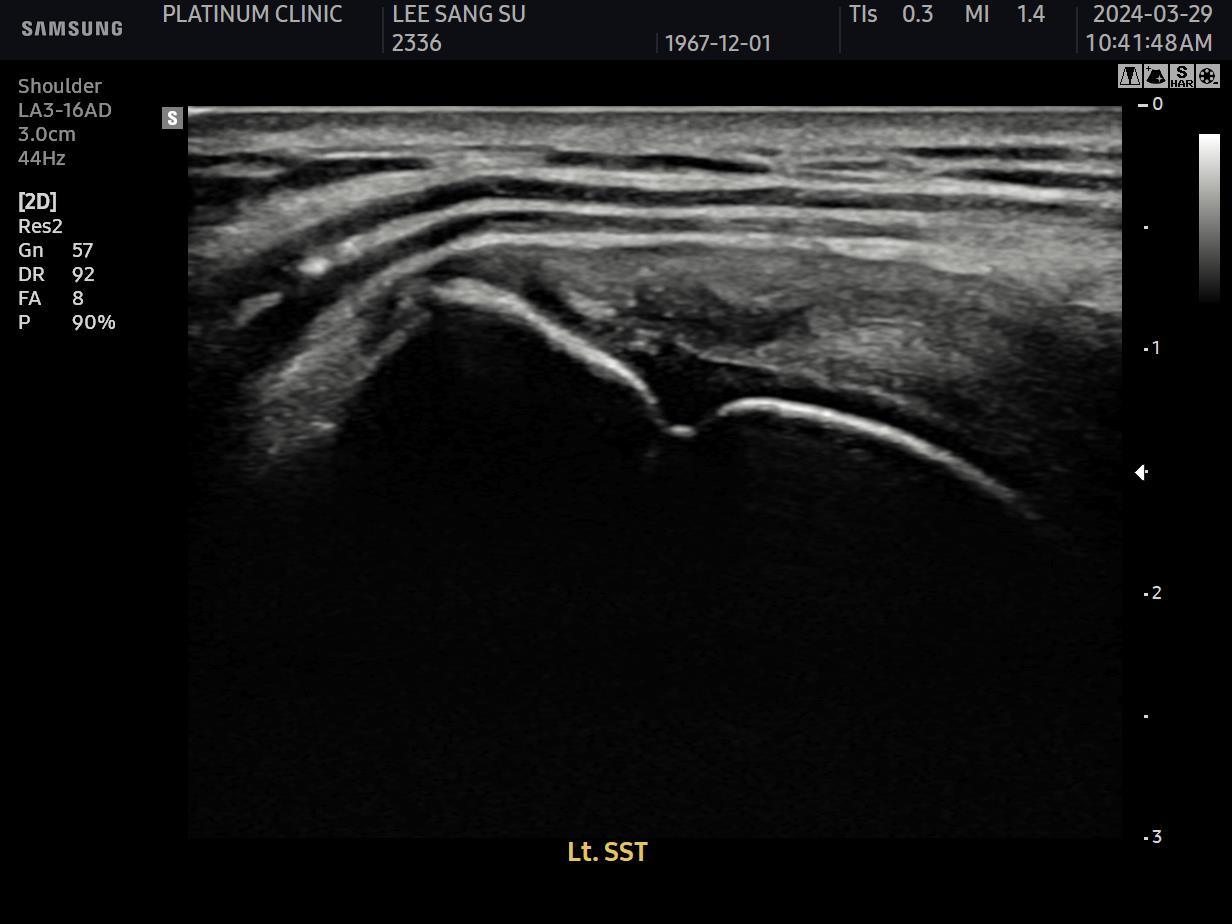

초음파 검사를 해보았습니다.

결과는 안타까웠습니다. 6개월 전보다 파열이 더 진행되어 있었습니다.

초음파 검사로 확인할 수 있습니다.

치료 전 초음파에서 검게 보이던 파열 부위가, 치료 후에는 정상 인대처럼 하얗게 보입니다. 이것이 구조적 회복의 증거입니다.

안 아파요"라는 주관적 느낌만으로 치료 완료를 판단하면 안 됩니다. 영상으로 확인된 구조적 회복이 있어야 진정한 치료입니다.

12주차: 초음파로 확인된 '재생'

마지막 주사로부터 6주 후, 팔로우업 검사를 진행했습니다.

초음파 결과:

이전에 검게 보이던 파열 부위가 하얗게 재생됨

인대 두께가 정상 범위로 회복됨

주변 염증 소견 소실